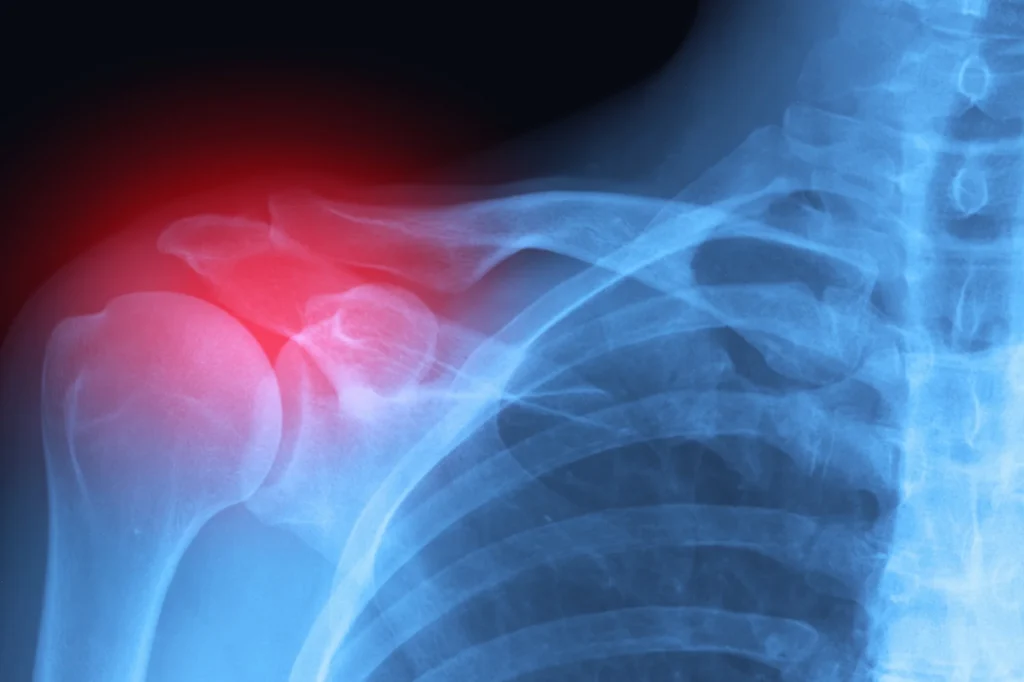

Imaging plays a key supporting role. X-rays are typically ordered first to reveal fractures and bone alignment issues. When soft tissue damage is suspected, such as a rotator cuff tear or labral injury, an MRI often provides the detailed view needed to confirm the diagnosis. In some complex fracture situations, a CT scan may help with surgical planning.